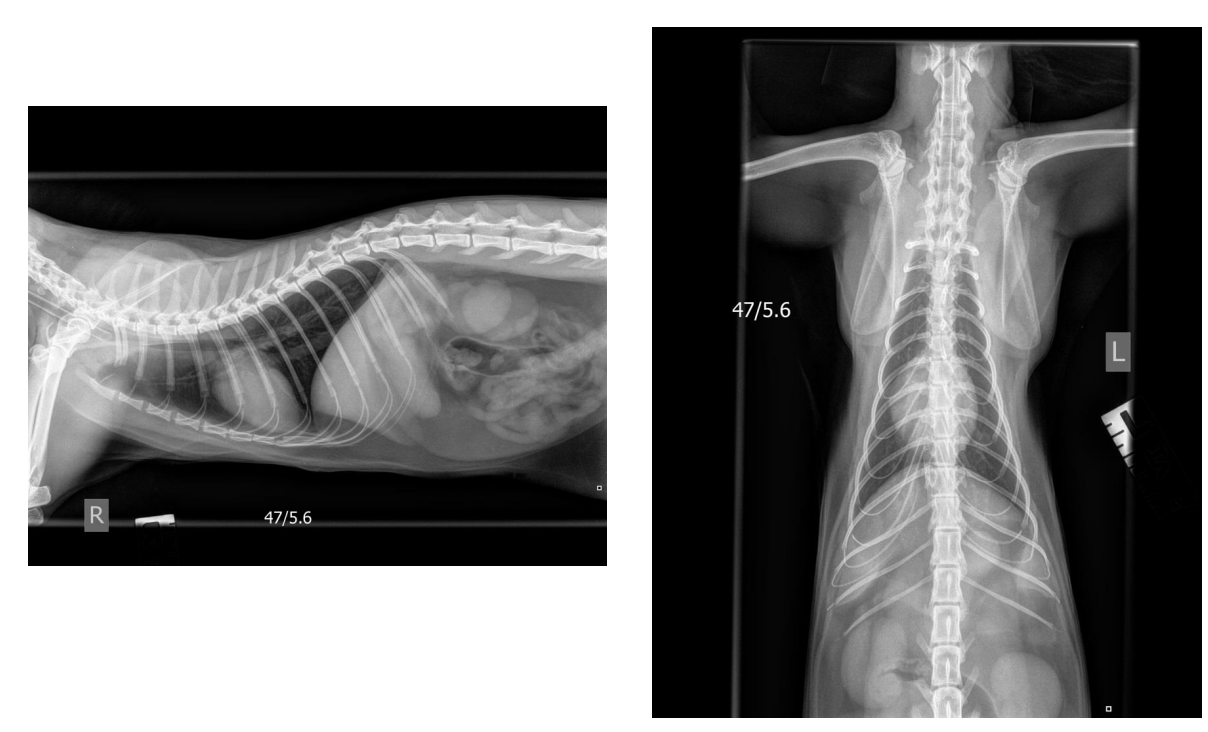

Why do you think the lungs look clearer in the L lateral view of one dog than the R lateral view of the other?

The lungs are better aerated in the L Lat view and therefore there is better contrast between the air filled lung and the vascular structures of the lungs and also the other soft tissue structures of the thorax.

This could be due to a number of reasons – stage of respiratory cycle image was taken at, GA v conscious dog, presence of respiratory disease, breed (eg. Brachycephalic) etc

what are the lines demonstrating

crura of the diaphragm parallel in right lateral view

heart long and in contact with sternum

what is demonstrated by the lines

crura of diaphragm V shaped left lateral

heart shorter, rounded and less contact with sternum